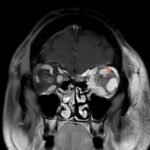

Orbital compartment syndrome (OCS) is an ophthalmologic emergency due to an acute rise in intra-orbital pressure and can result in permanent vision loss, oftentimes requiring emergent surgical decompression. Orbital compartment syndrome most commonly occurs due to recent trauma and is often easily diagnosed by history and physical exam. However, there are other causes of OCS where a more subacute/chronic rise in pressure can lead to an atypical presentation. This is a case report of a 48-year-old male who presented with left eye pain and swelling for the past 6 months. The patient had seen two ophthalmologists prior to his emergency department (ED) presentation who had prescribed him an antibiotic ointment, oral steroids, and steroid eye drops. The physical exam in the ED was concerning for increased intra-ocular pressure (IOP) and decreased vision. Ophthalmology was consulted and requested magnetic resonance angiography (MRA) to assess a vascular etiology given tortuous retinal vasculature. Emergent surgical decompression was deferred due to chronicity of symptoms, and patient was started on dorzolamide/timolol and brimonidine eye drops as well as intravenous (IV) acetazolamide with subsequent improvement in IOP. Imaging revealed a left carotid-cavernous sinus fistula (CCF), and the patient was admitted to neurosurgery. Patient successfully had an embolization with subsequent normalization of IOP and improvement of symptoms. This case is a good example of how non-traumatic causes of OCS can lead to misdiagnosis and how surgical decompression could potentially be deferred in subacute OCS.